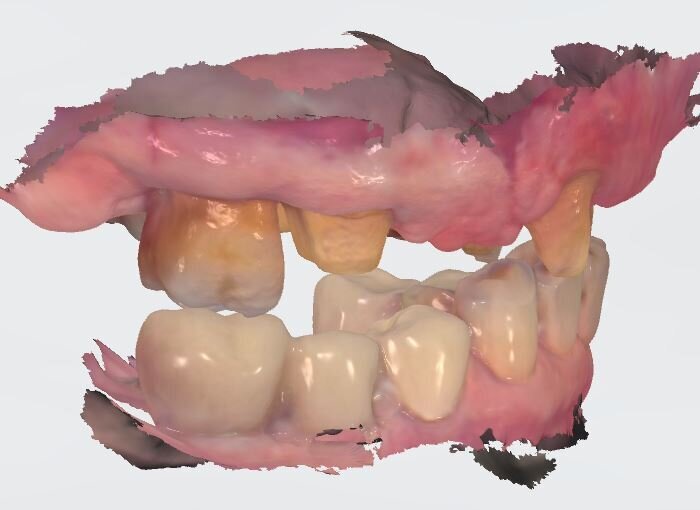

In laboratorio, l’odontotecnico su nostra indicazione potrà elaborare i file ricevuti, valutando la possibilità di avvitare direttamente il manufatto, solo in caso di forte disparallelismo si opterà per la cementazione. Definita la procedura, verrà realizzato solo il provvisorio su impianti modificando il primo provvisorio che sarà riposizionato dopo il sezionamento dei quadranti (Figg. 27, 28). Dopo il posizionamento del nuovo provvisorio rileviamo una nuova impronta studio (Fig. 29) che analizziamo col software dedicato dello scanner digitale utilizzato.

I dati raccolti sono molti ma la procedura digitale consente di sommarli e confrontarli senza limiti e indicando le possibili migliori e correzioni lungo il percorso. Dopo un breve periodo di condizionamento dei tessuti (Fig. 30) rileviamo l’impronta master per la finalizzazione ultima della riabilitazione protesica. L’impronta degli elementi naturali viene rilevata posizionando dei fili detrattori secondo la tecnica del doppio filo mentre per gli impianti verranno usati gli scan body dedicati (Fig. 31). Le potenzialità digitali consentiranno di avere una stabile lettura della posizione di centrica rilevandola prima della rimozione dei provvisori e sovrapponendola a provvisori rimossi (Fig. 32). In laboratorio l’odontotecnico realizza i modelli (Figg. 33, 34) sovrappone le immagini (Fig. 35) e raccoglie gli elaborati dei vari passaggi che porteranno alla finalizzazione del progetto digitale (Figg. 36, 37).

Fig. 29_A provvisorio posizionato abbiamo rilevato le impronte per definire la corretta posizione coronale e l’emergenza estetica.